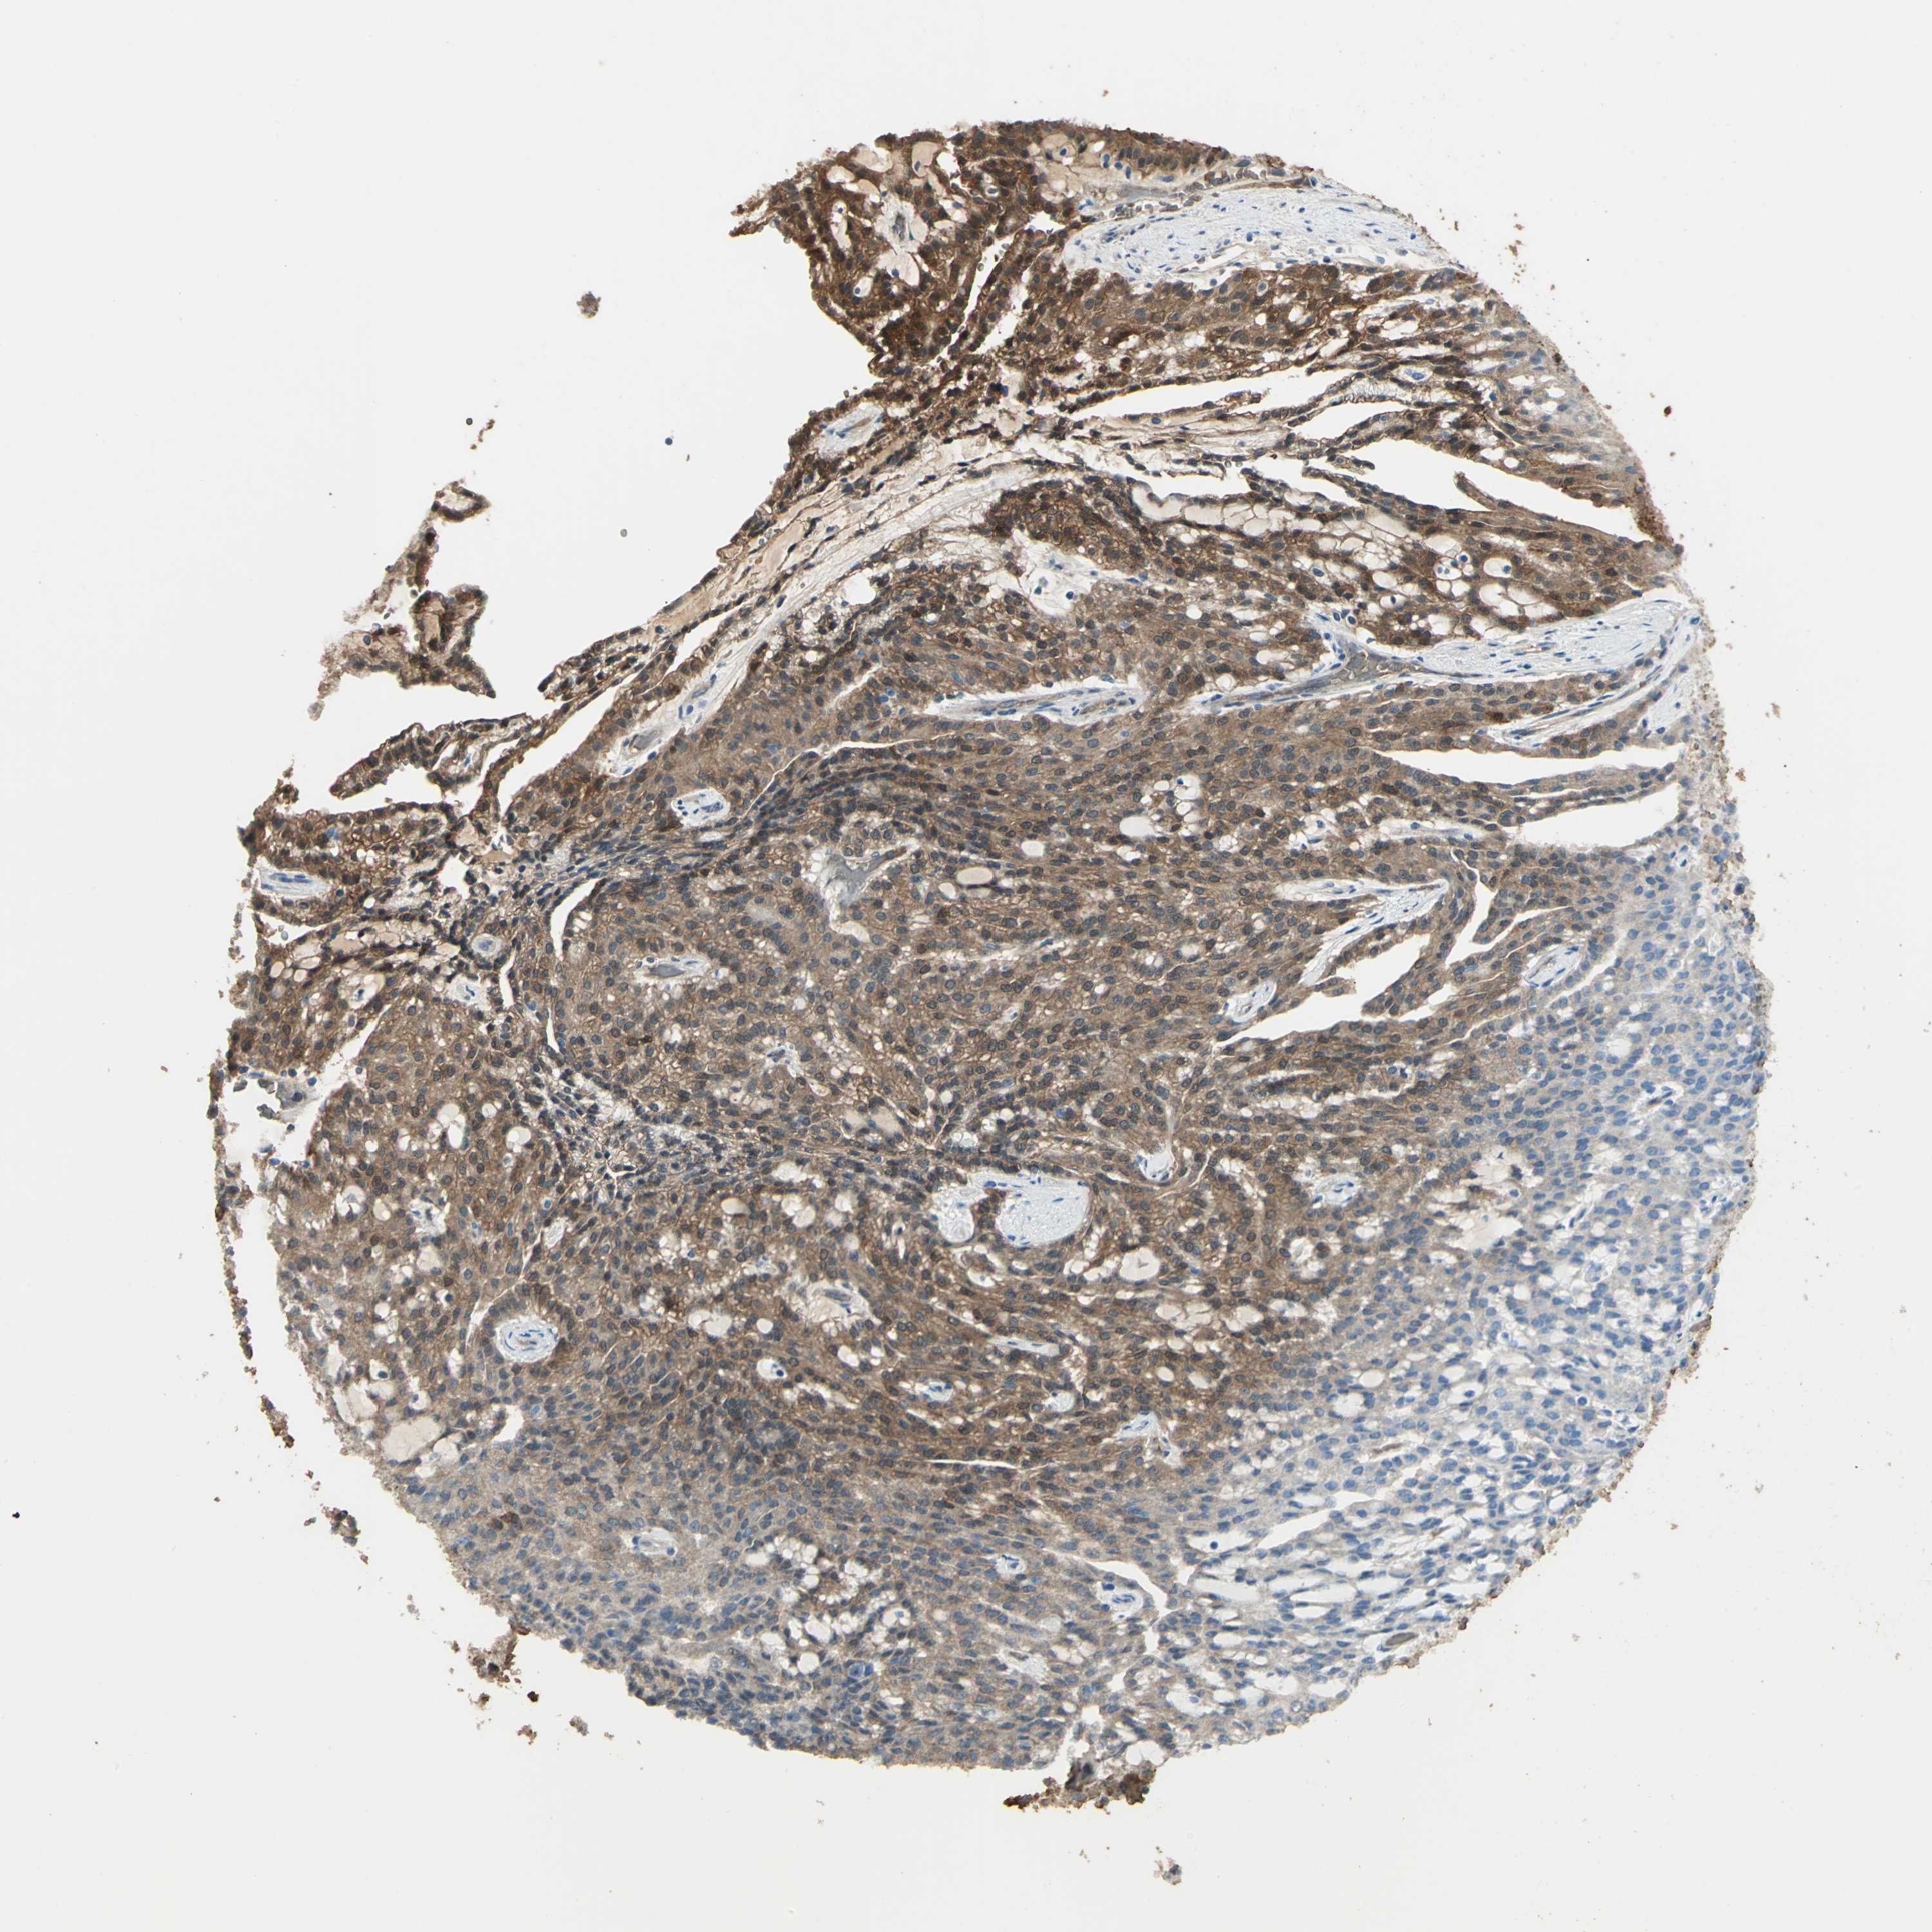

CANCER RENAL CANCER Show tissue menu

KICH TCGA KIRC TCGA KIRC VALIDATION KIRP TCGA PROTEIN RCC CPTAC PROTEIN EXPRESSION

Renal cancer

Kidney renal clear cell carcinoma

DDAH1 is validated prognostic, high expression is favorable in Kidney Renal Clear Cell Carcinoma (TCGA)